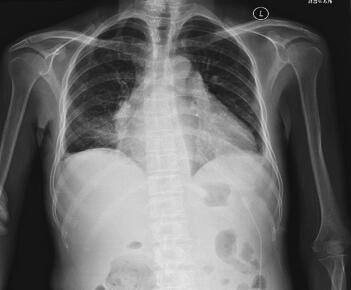

患者症状明显好转,4月18日复查免疫球蛋白IgA<0.07g/L,IgG 2.21g/L(好转),IgM<0.04g/L,CRP 75.1mg/L。4月20日复查超声心动图:少量心包积液,仍可见纤维素渗出,心包脏层回声粗糙;4月22日复查腹部B超:PV内径1.2cm,较前无明显变化。患者心包积液逐渐减少,为防止形成缩窄性心包炎,需考虑外科行心包剥脱术治疗,心外科考虑如行心包剥脱术,需体外循环,但患者体液免疫能力过差,行体外循环风险极大,考虑患者无法耐受手术,不予手术治疗。4月26日复查血常规:WBC 4.92×109/L,N 62.1%,RBC 4.92×1012/L,Hb 110g/L;肝肾功能、电解质明显好转;凝血功能未见异常;尿常规未见异常。4月28日复查胸片:右肺下野片状高密度影,心影增大,较前有所好转(图3)。

图3 胸片:右肺下野片状高密度影,心影增大,较前有所好转